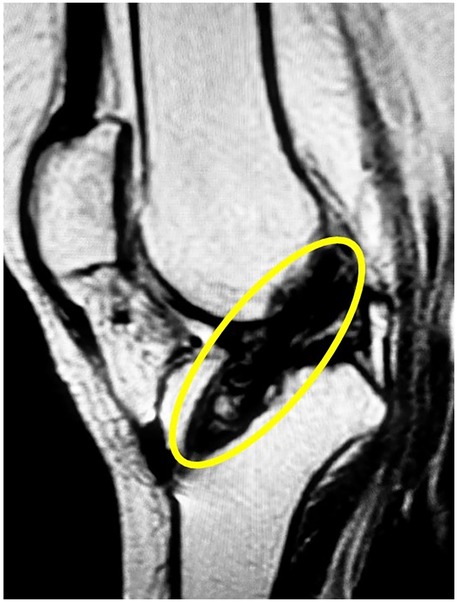

Following her recovery from initial injuries, the patient underwent long-term physiotherapy and rehabilitation for her spinal cord injury. Her paraplegia improved significantly, allowing her to stand and take assisted steps with a specialized walker. However, she reported instability in her right knee, which often gave way and hindered her walking progress. Clinical examination confirmed a complete ACL rupture in the right knee, later verified by magnetic resonance imaging (MRI). Physical exam showed moderate quadriceps atrophy, graded as Goutallier Grade 2. Instrumented laxity testing with the KT-1000 arthrometer indicated 5.2 mm of anterior tibial translation compared to the opposite side, confirming mechanical instability. MRI, performed with a 3 mm slice thickness, revealed high signal intensity on T2-weighted sequences consistent with mucoid degeneration. During diagnostic arthroscopy, about 45% of the ACL and 40% of the PCL fibers showed fraying and were debrided, while remaining ligament fibers were preserved to maintain residual tension and joint proprioception. Pre-operative imaging was crucial for assessing the ACL injury and planning the surgery, while post-operative imaging confirmed accurate graft placement and alignment with surrounding structures. These images validated the surgical outcome and provided a clear assessment of graft integrity. Figures include pre-operative MRI showing the ACL rupture (Figure 1) and post-operative (1-year) imaging demonstrating a successful, intact, and functional ACL (Figure 2).

Figure 1

MRI scan showing a knee joint in a sagittal view, with a yellow circle highlighting an area of interest near the ligaments, possibly indicating an abnormality or injury.

Figure 1. Pre-operative MRI showing complete ACL rupture in a paraplegic patient.